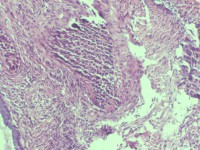

性别

女

年龄

43岁

临床诊断

宫颈病变

一般病史

宫颈癌筛查:hpv16(+))

标本名称

宫颈组织

大体所见

灰白色组织

老师们看看,高级别累腺吗

高级别累腺,不除外局灶早期浸润

高级别累及腺体